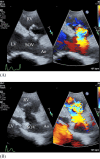

Ruptured sinus of Valsalva aneurysm (RSOVA) is a rare cardiac condition associated with high morbidity and mortality rates. We herein report a 35-year-old man with a history of ventricular septal defect (VSD). He had a history of interrupted hospital visits and presented to the emergency department with dyspnea, palpitations, and dizziness for a few days. Auscultation detected a continuous murmur. Transthoracic echocardiography followed by transesophageal echocardiography demonstrated RSOVA in the right ventricle with an aorto-right ventricular fistula. The fistula was resected, and the aneurysm was surgically repaired. The patient made a good recovery.